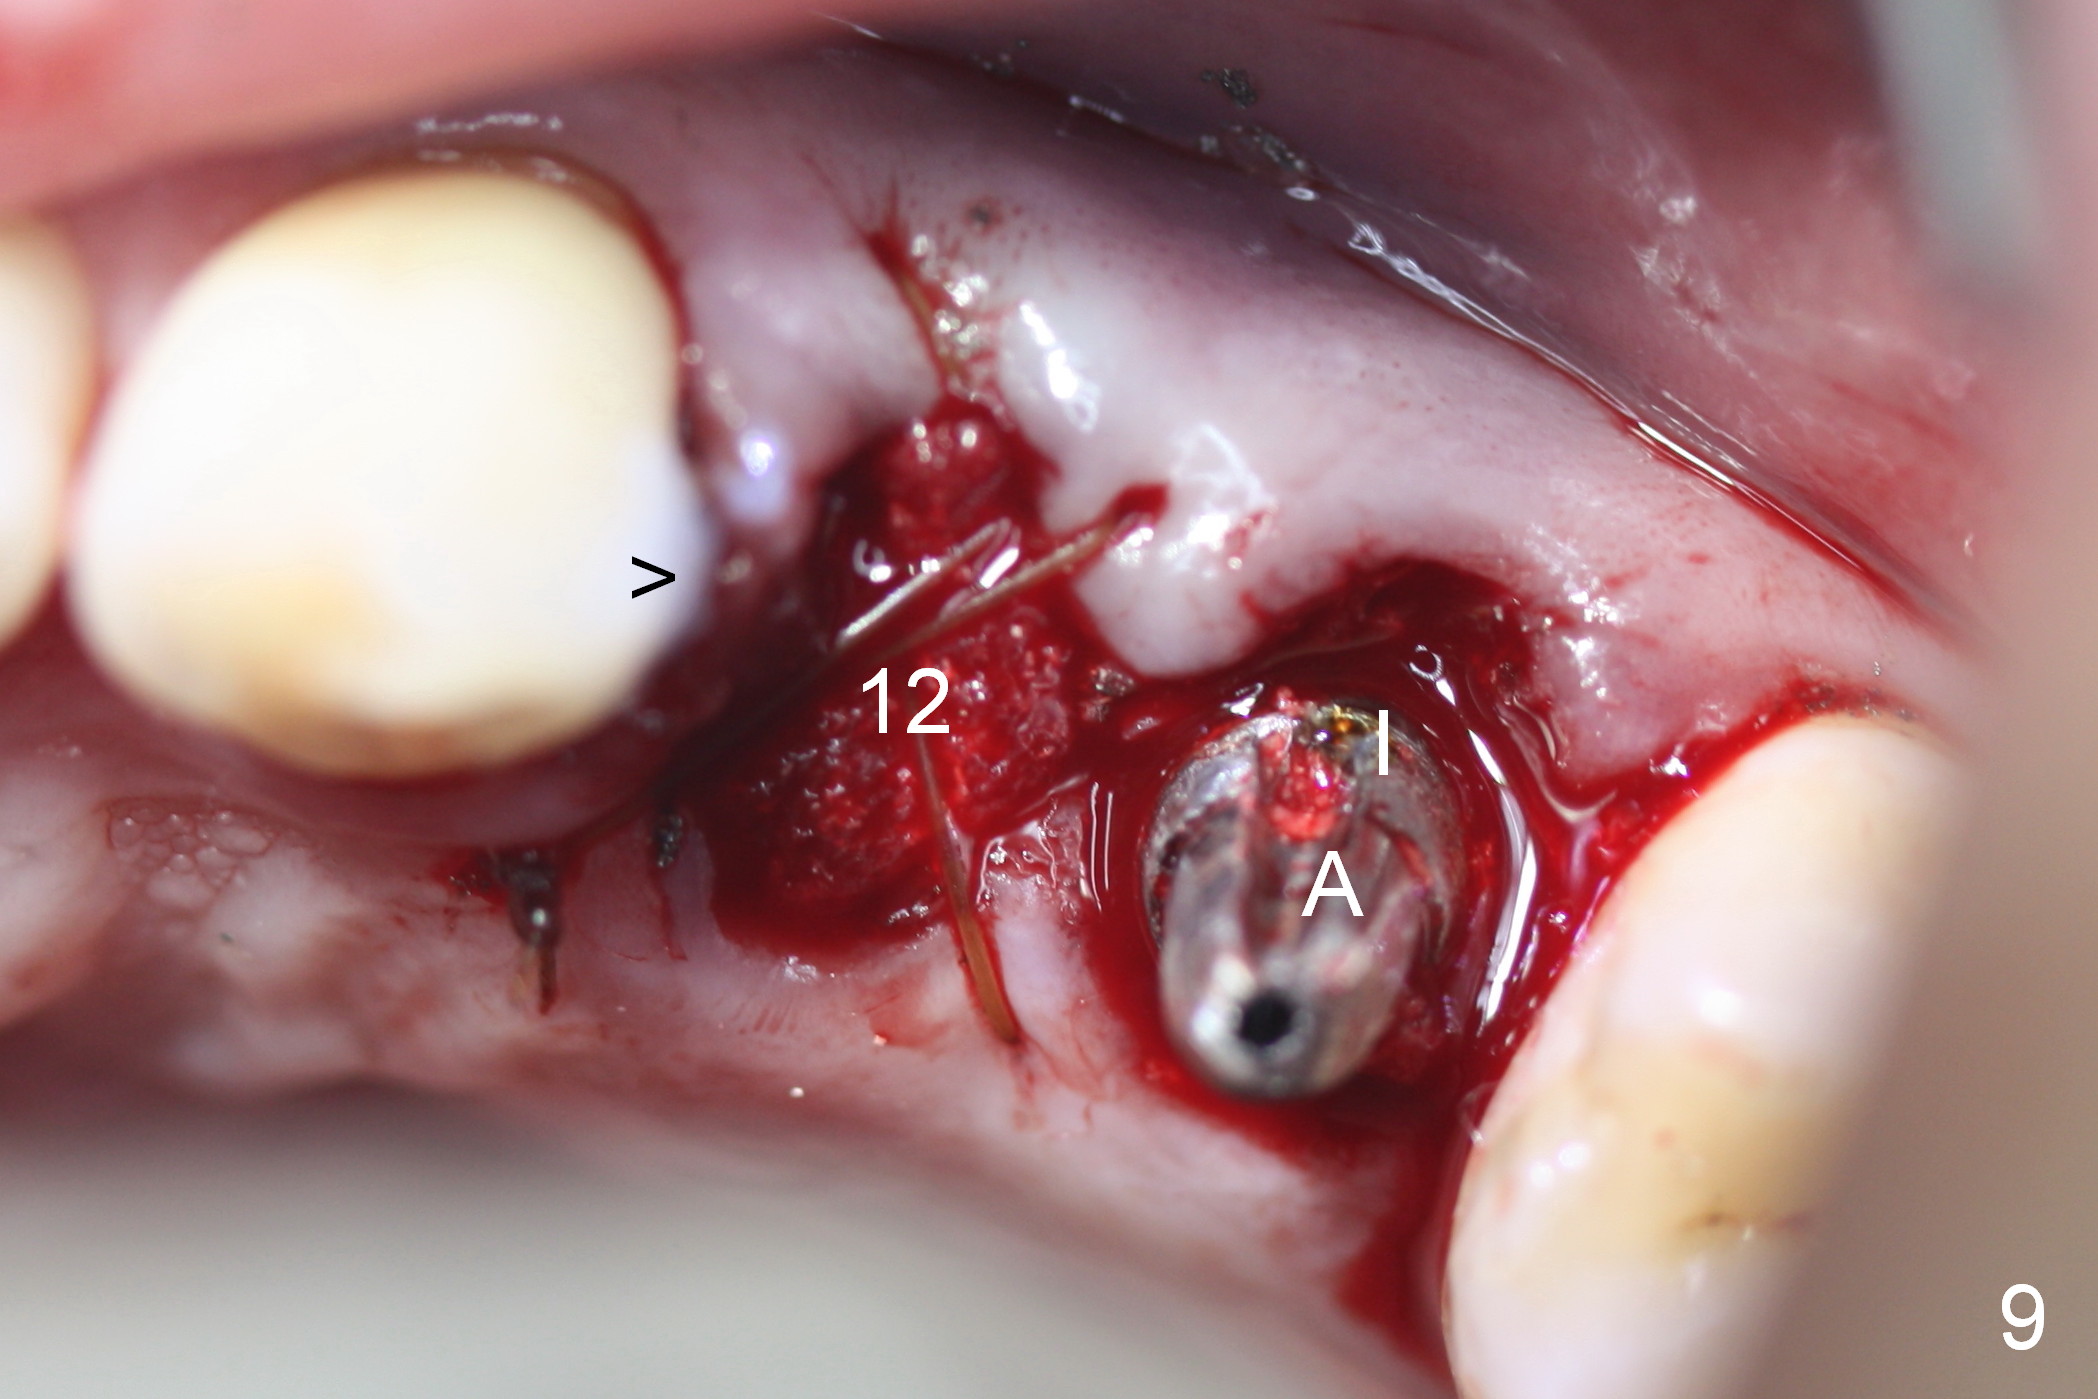

Taking 2 additional PAs with sensor 1 is frustrating (Fig.1,2), no apices shown. Osteotomy is done smoothly with 2 mm pilot drill at 20 mm, 2.5 mm reamer at 17 mm, and 3 mm reamer at 14 mm and 4.5x20 mm tap at 17 mm. The 1st intraop PA is taken with sensor 1 when 2 of 4.5x20 mm implants are placed (Fig.3); the implant at #12 is close to the root of the tooth #11. The 2nd PA is taken with sensor 2: the apex of #11 touches the implant at #12 (Fig.4). There is no separation when panoramic X-ray is taken (Fig.5). Effort is exerted to re-direct the osteotomy twice (Fig.6: tap; Fig.7: implant) without success. When the implant is removed, a PA is taken; it appears that the root of the tooth #11 has no damage (Fig.8). To obtain the best recovery, socket preservation is carried out with 50/50 cortical/cancellous allograft mixed with Osteogen (Fig.12 *) and Collagen Dressing (Fig.9: #12). A 2 (or 3)-unit provisional bridge (Fig.10: #12,13) is fabricated over the implant (Fig.9 I)/abutment (A) to cover these 2 sockets. After acid etching #11 D surface (Fig.9 >) and relining (Fig.11 *), the provisional bridge is bonded to the tooth #11 (Fig.11,12 black >) so that bone graft will be less likely dislodged.